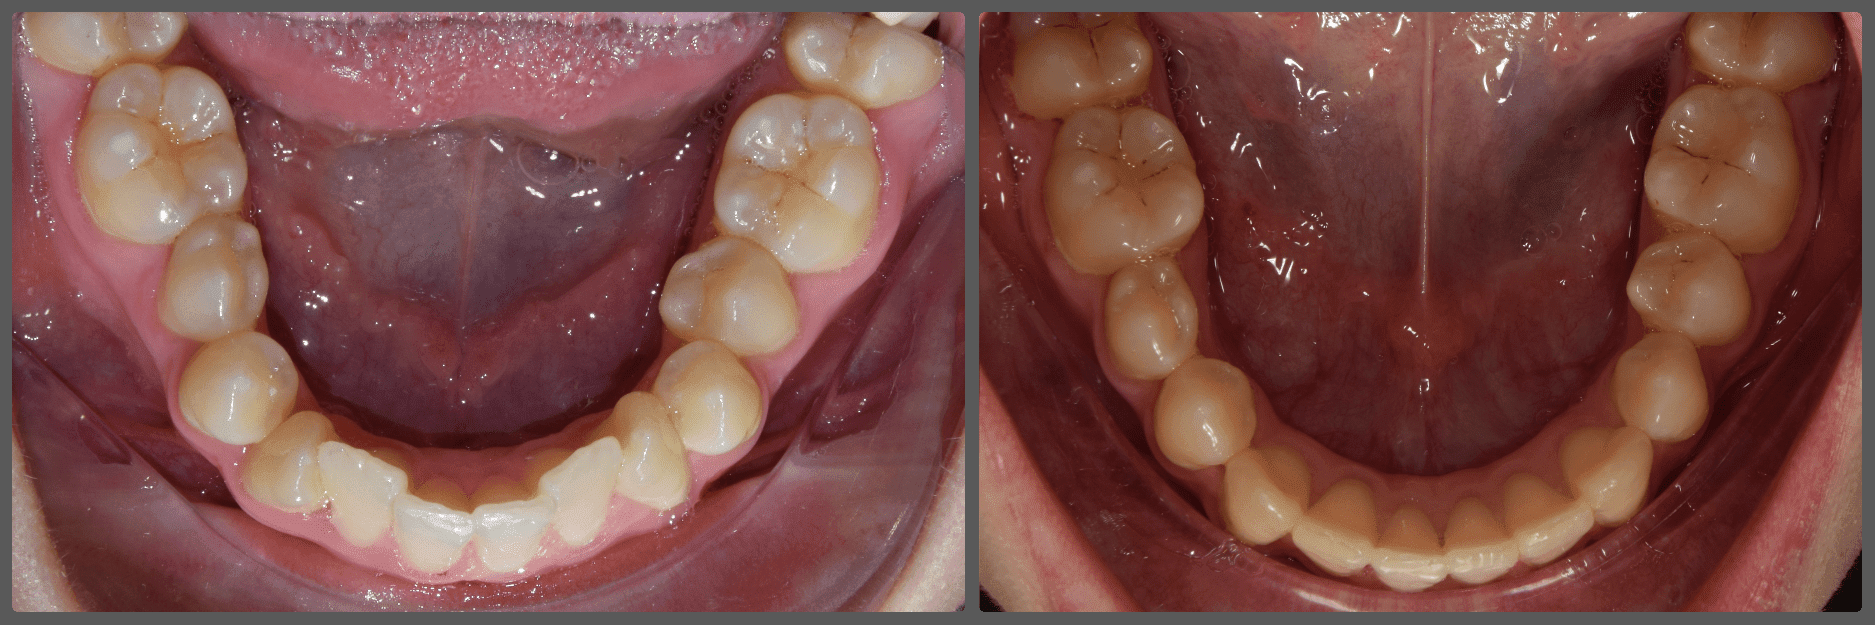

Florina alsó foghiányai és enyhe torlódása miatt szeretett volna fogszabályozó készüléket. A felső fogívben jelentős rágósíkbillenést, valamint az alsó fogívben a hiányzó első nagyőrlők helyére bedőlt/előre vándorolt második nagyőrlő fogakat diagnosztizáltam. H4 önligírozó fogszabályzó készülék, harapásemelők és intermaxilláris gumihúzás használatával korrigáltuk a rágósík billenést, illetve az enyhe harapási eltérést. Az alsó második nagyőrlőket tolórugó segítségével ideális pozícióba helyeztük, az első nagyőrlő fogak helyét pedig optimalizáltuk implantációs fogpótlás behelyezésére. A kezelés 13 hónapig tartott.